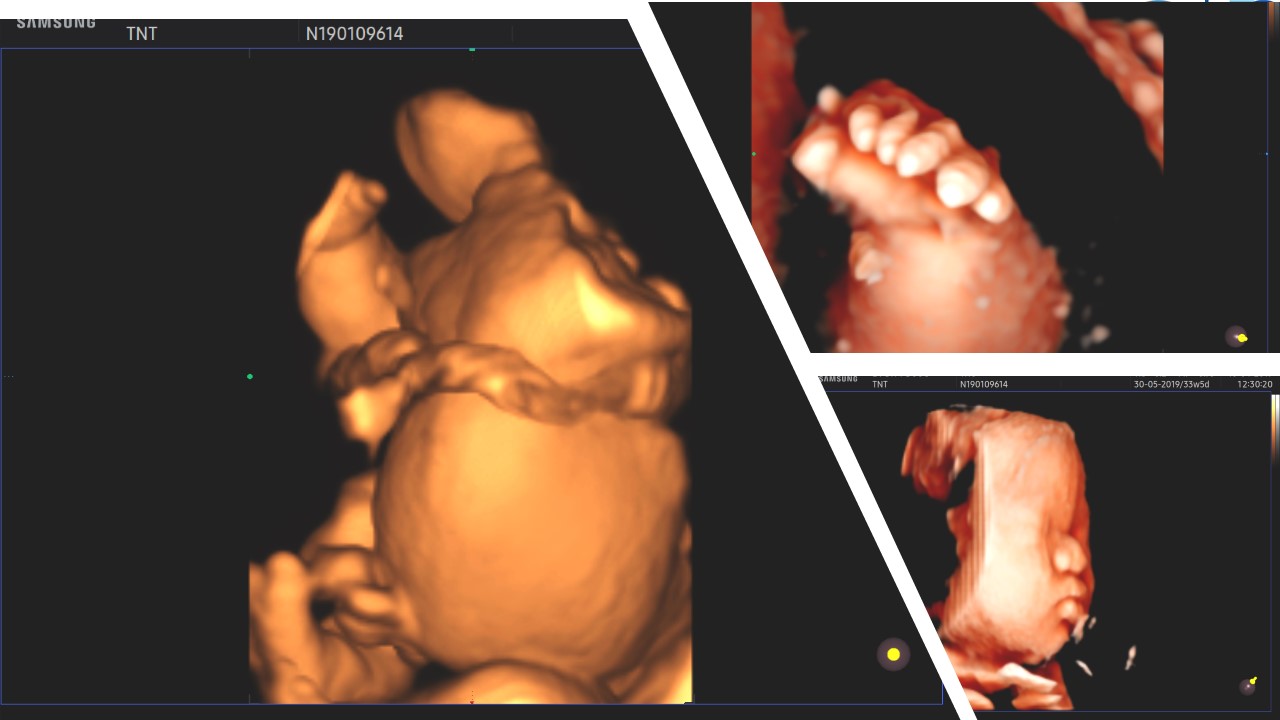

CES - clinical exome sequencing, Tiếp cận mới trong chẩn đoán trước sinh

Trần Nhật Thăng, BM Phụ sản, Khoa Phụ Sản - BV Đại học Y dược TP. HCM